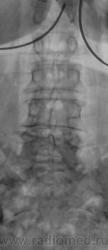

1. пациентка

2. форма позвонка - односторонне-вогнутая

3. контуры "вдавления" верхней замыкательной пластинки относительно четкие

4. елементы слероза по контуру "вдавления"

Пациентке 65 лет. Клиника радикулита.

тоже увиделись такие же характеристики зоны интереса, да и м\п диск снижен в этом сегменте + диф. остеопороз = может это такая грыжа диска?

В первую очередь думаю о негативных последствиях постменопаузального остеопороза (такая форма позвонков при патологической их компрессии вполне возможна).

4 - на Т-грамме не понравились замыкат. пластинки (больше краниальная) И L6 (И смежные L2, L3 - в последних, возможно, грыжевые вдавления)...

Сколиоз, остеохондроз, большая красивая центральная грыжа Шморля и сужение межпозвонковых отверстий. Вполне достаточно для клиники радикулита.